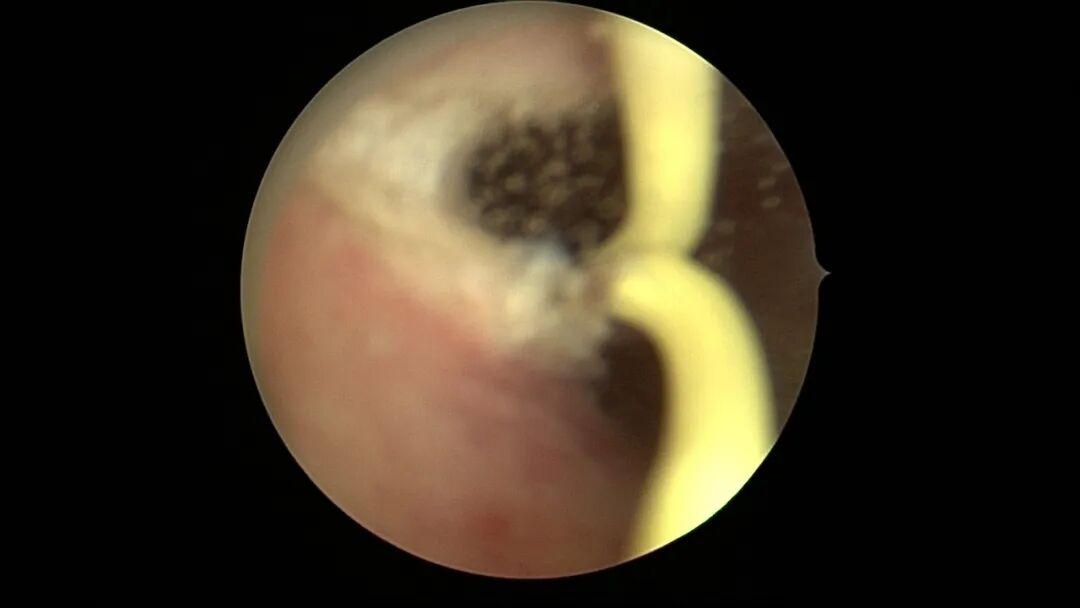

第一次宫腔镜:2021年4月,闭经50+天,B超提示宫腔粘连,宫腔镜探查见宫颈管上段封闭粘连,宫腔广泛粘连,AFS评12分(最高分)。宫腔镜单极电切分粘,恢复宫腔形态,显露双侧输卵管开口,右侧宫角附近内膜柔软、红润,宫腔防粘连复发处理。